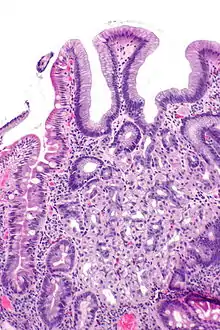

![]() صورة مجهرية تُظهر خزعة إثنا عشرية مع توضع معوي مغاير، وهي مصبوغة بصبغة الهيماتوكسيلين واليوزين. صورة مجهرية تُظهر خزعة إثنا عشرية مع توضع معوي مغاير، وهي مصبوغة بصبغة الهيماتوكسيلين واليوزين. | |